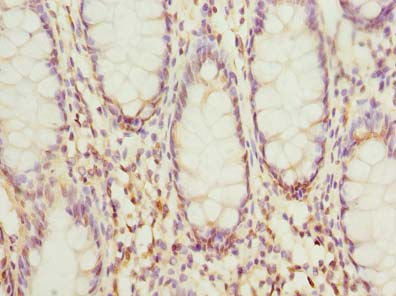

ApplicationELISA, WB, IHC; Recommended dilution: WB:1:500-1:2000, IHC:1:20-1:200